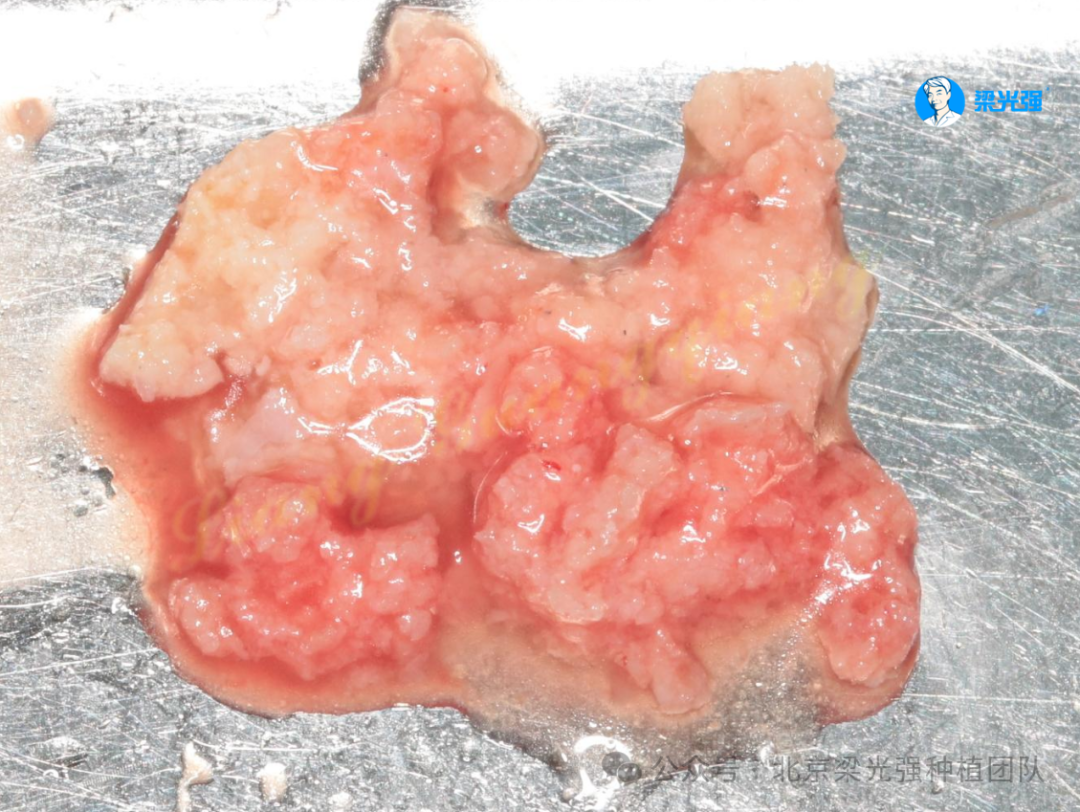

牙槽嵴顶用金刚砂车针去除上皮层。

图片

安装愈合基台将去上皮的角化龈折叠翻转推到唇侧,以增加唇侧附着龈厚度。